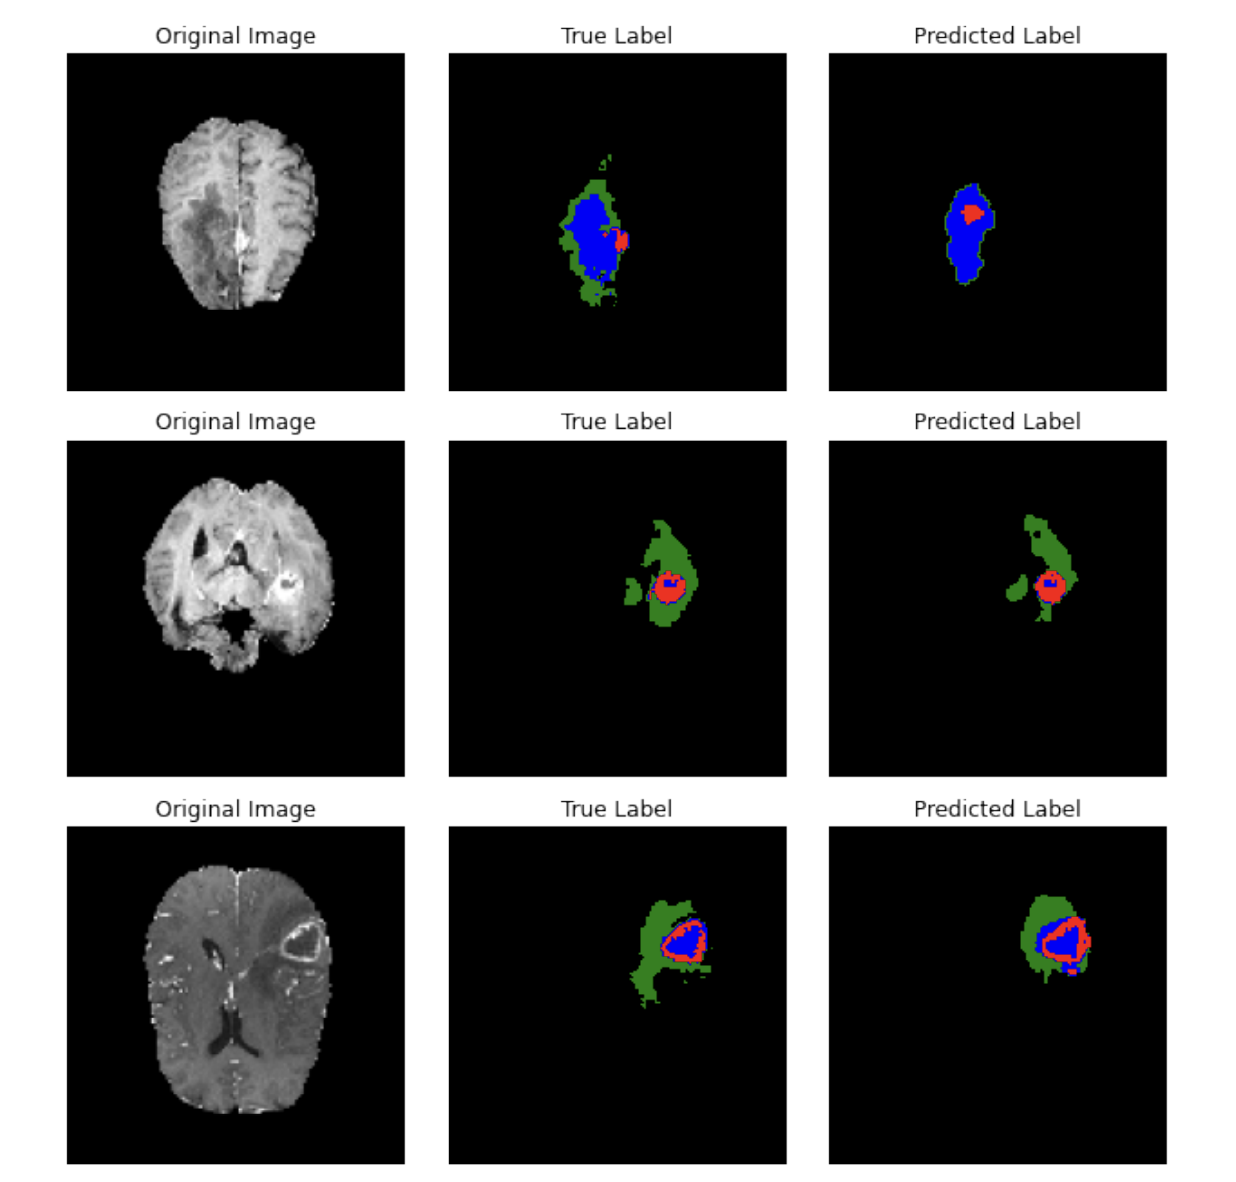

• Implemented a 3 layer U-Net and trained it using Grayscale brain scans and tumor segmentation images.

• Achieved a final test loss of 0.042, with the model being able to predict and identify the tumorous regions of the brain with high accuracy.